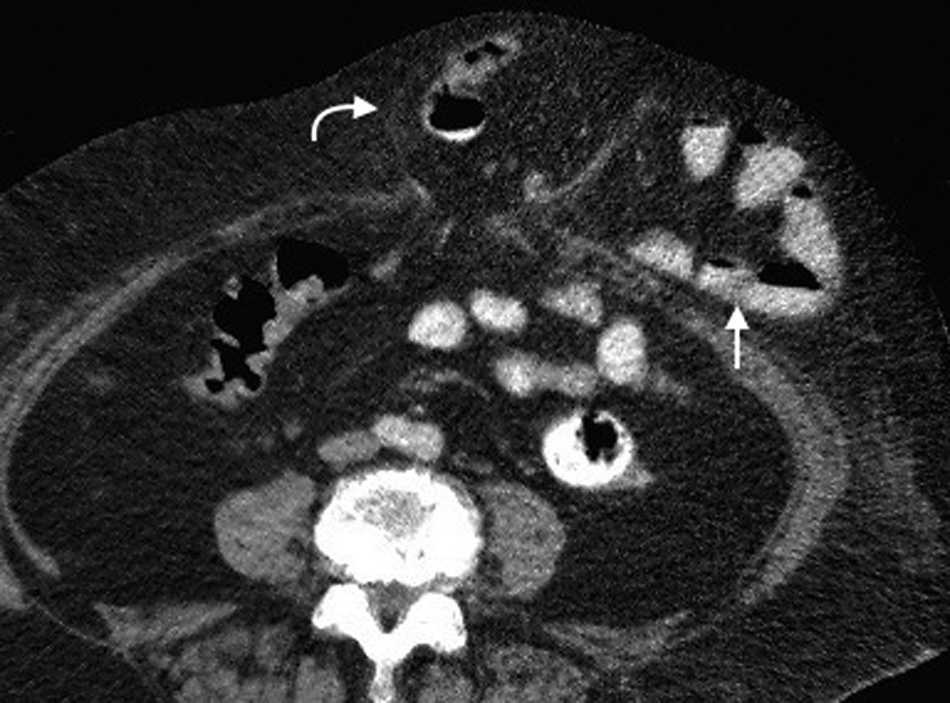

Su diagnástico clínico es difícil porque su incidencia es infrecuente, su localizaci??n profunda y tiene pocos signos o s??ntomas espec??ficos, como los relacionados con la compresi??n del nervio obturador (signo de Howship-Rombeng)10. El foramen obturador se conforma por la continuidad de los huesos isqui??ticos y p??bicos, y est?? cubierto por la membrana obturatriz, excepto en el receso anterosuperior donde es perforada por la arteria, la vena y el nervio obturador, que viajan a lo largo del t??nel de 2-3 cm formado por los m??sculos obturadores internos y externos. A trav??s de este defecto, se produce la hernia peritoneal11.

Es m??s com??n en mujeres mult??paras de edad avanzada debido a la debilidad generada en el piso p??lvico, aunque tambi??n se ve en pacientes con aumento de la presi??n abdominal y ancianos debilitados1.

Su diagn??stico espec??fico se puede hacer si en la TCMD de pelvis se visualiza el intestino herniado entre los m??sculos pect??neo y obturador externo con obstrucci??n del intestino delgado sin una causa aparente3 (fig. 4).